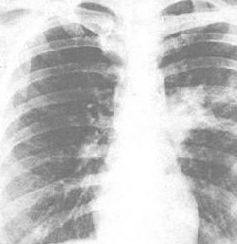

合胞病毒肺炎主要以陣發性喘憋和伴有兩肺廣泛的喘鳴音為臨床特點。一般在感染合胞病毒後,經3~5日的潛伏期,即出現上呼吸道症狀,如咳嗽、鼻塞等。發熱一般不高,甚至可不發熱,但部分病人可高熱。多數病例的熱程為4~10天,少數持續10日以上。患兒咳嗽、呼吸困難、鼻扇、發紺及三凹征明顯。並常有陣發性喘憋,發作時呼吸淺快,伴呼氣性呻吟和喘鳴,面色蒼白,額出汗。肺部叩診呈過清音,聽診呼吸音減弱,有彌散的喘鳴音及中、細濕羅音。肝脾常因肺氣腫而被推向肋緣下。由於喘引起PaO2、SaO2降低及PaCO2上升,而發生呼吸性酸中毒,重症可並發呼吸衰竭及心力衰竭,甚至窒息死亡,尤在先天性心臟病患兒病死率高。

X線檢查主要示間質性肺炎、肺氣腫及肺泡病變,多為小點片狀陰影,少數呈塊狀陰影,可融合,邊緣模糊不清。肺野外帶透明度增高,可伴局部肺不張或局限性肺氣腫。